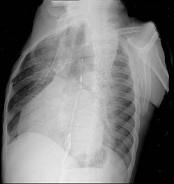

问题 56岁男性患者,劳累后心慌气促10余年,近来自觉症状加重。临床听诊,心尖区有舒张期隆隆样杂音,行胸部X检查,如图所示,你认为下列描述正确的是 ( )

选项 A、考虑三尖瓣狭窄 B、考虑二尖瓣狭窄 C、右前斜位示左心房增大,心后上缘后突压迫冲钡食管 D、左前斜位示心影向后下方突出 E、后前位示双侧肺血增多,肺动脉段隆起,左心缘出现第3弓

答案 BCDE